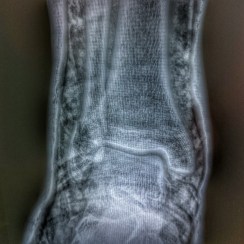

Una fractura, tal i com el seu nom indica és un trencament d’un os, presentant dolor localitzat, impotència funcional i inflamació.

Les formes més comunes de fractures són tres: tancades, de “tija verda” i obertes. Continua llegint